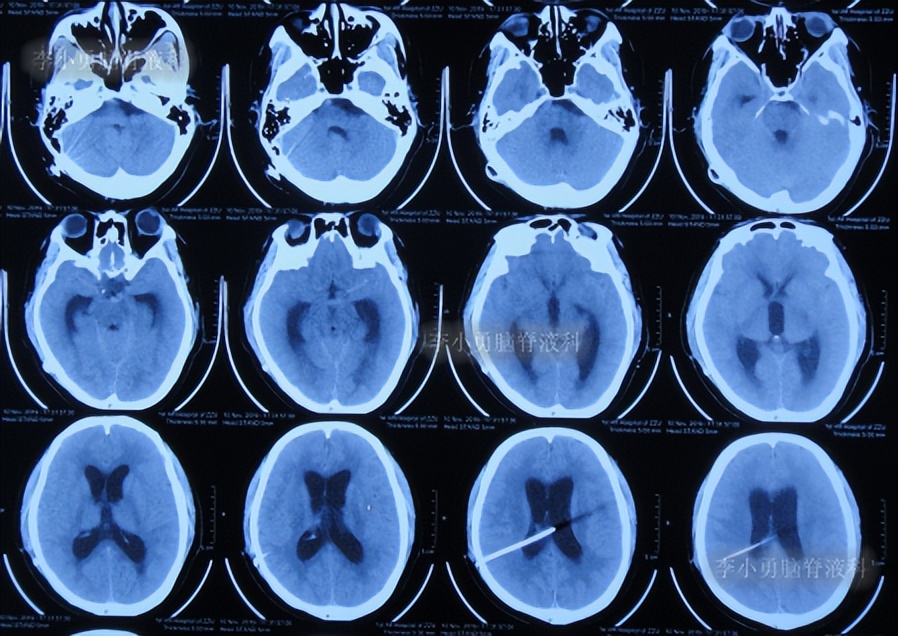

第4次出院后2个月时间内,期间曾4次查头颅影像均示脑室有进一步扩张(图-12、图-13、图-14、图-15),且患者精神逐渐变差。

图-12:2020年3月14日头颅CT

图-13:2020年3月31日头颅核磁

图-14:2020年4月18日头颅CT

图-15:2020年5月9日头颅核磁